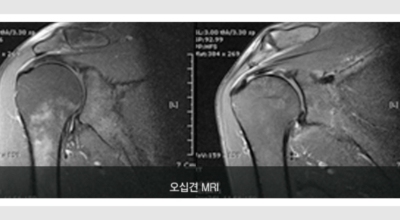

오십견이란?

오십견이란 어깨의 통증과 어깨관절의 운동범위 제한을 특징으로 하는 질환으로 특히 50대 이후에 많이 발생함으로 오십견이라 이름이 지어졌으며 어깨관절이 얼어붙었다는 뜻으로 동결견(frozen shoulder)이라고도 합니다. 어깨관절의 운동성이 소실되기 때문에 옷 입기, 머리 감기, 물건 들기 등의 일상생활에 많은 어려움이 유발되며 통증에 의하여 잠을 못자는 경우도 대개 발생하게 됩니다.